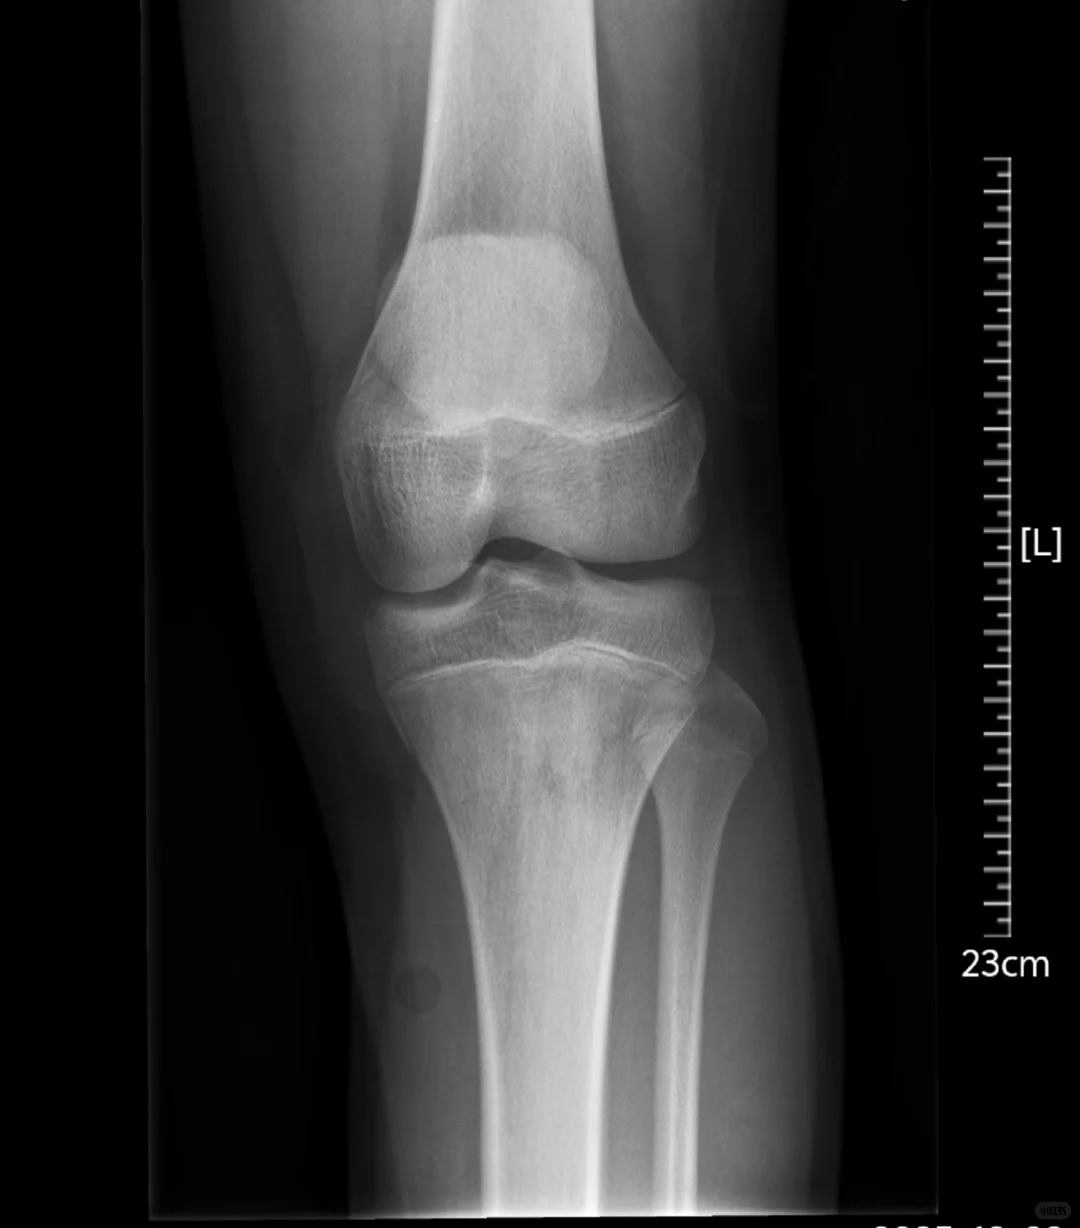

医生根据ct结果总结左胫骨平台见骨折线,其断端无分离及成角,周围软组织稍肿胀,余左膝关节诸骨未见骨折及脱位征